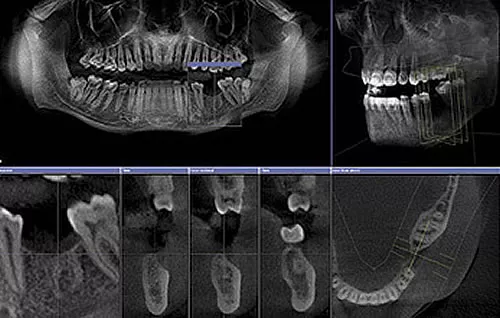

RÖNTGENDIAGNOSTIK

Warum reicht ein 2D-Röntgen manchmal nicht aus?

Oft klagen Patient:innen über Zahnschmerzen, doch auf einem herkömmlichen zweidimensionalen Röntgenbild (Einzelbild oder Panoramaaufnahme) ist keine eindeutige Ursache erkennbar. Das liegt nicht an einem Diagnosefehler des Zahnarztes – sondern daran, dass räumliche Tiefe (die 3. Dimension) auf solchen Bildern nicht darstellbar ist.

Beispiel:

Ein Zahn scheint auf dem 2D-Bild unauffällig. Doch das 3D-Röntgen (DVT) zeigt, dass eine der Wurzeln sich in einem knochenfreien Bereich befindet – ein eindeutiger Hinweis auf Entzündung oder Knochenabbau.

3D-Röntgendiagnostik mit DVT – exakte Einblicke in den Kiefer

Das digitale Volumentomogramm (DVT) ermöglicht eine dreidimensionale Darstellung des Kiefers. Damit erkennt man:

• Welche Wurzel betroffen ist (buccal oder palatinal)

• Das genaue Ausmass von Knochenabbau

• Entzündungsherde, die im 2D-Bild unsichtbar bleiben

• Anatomische Strukturen für präzise Implantatplanung

DVT statt CT:

Früher war das CT (Computertomographie) die einzige Möglichkeit für 3D-Diagnostik, aber mit hoher Strahlendosis und hohen Kosten. Heute bietet das DVT eine deutlich geringere Strahlenbelastung – vergleichbar mit einem digitalen Panoramaröntgen – bei präziser 3D-Bildgebung.

Fortschrittliche Technik – geringer Preis: das DVT «Galileos»

In der ACC Zahnklinik kommt das hochmoderne DVT-System «Galileos» zum Einsatz – benannt nach dem Astronomen Galileo Galilei. Es vereint:

• 3D-Röntgen (DVT)

• Panoramaaufnahme (OPT)

• Kleinröntgen zur Kariesdiagnostik

...alles in einem einzigen Scan – mit minimaler Strahlenbelastung und geringeren Kosten als konventionelle Methoden.

Auch bei der Implantatplanung wird das DVT eingesetzt: Die Implantate werden virtuell geplant und mittels computergestützter Bohrschablonen präzise gesetzt (statische Implantologie).